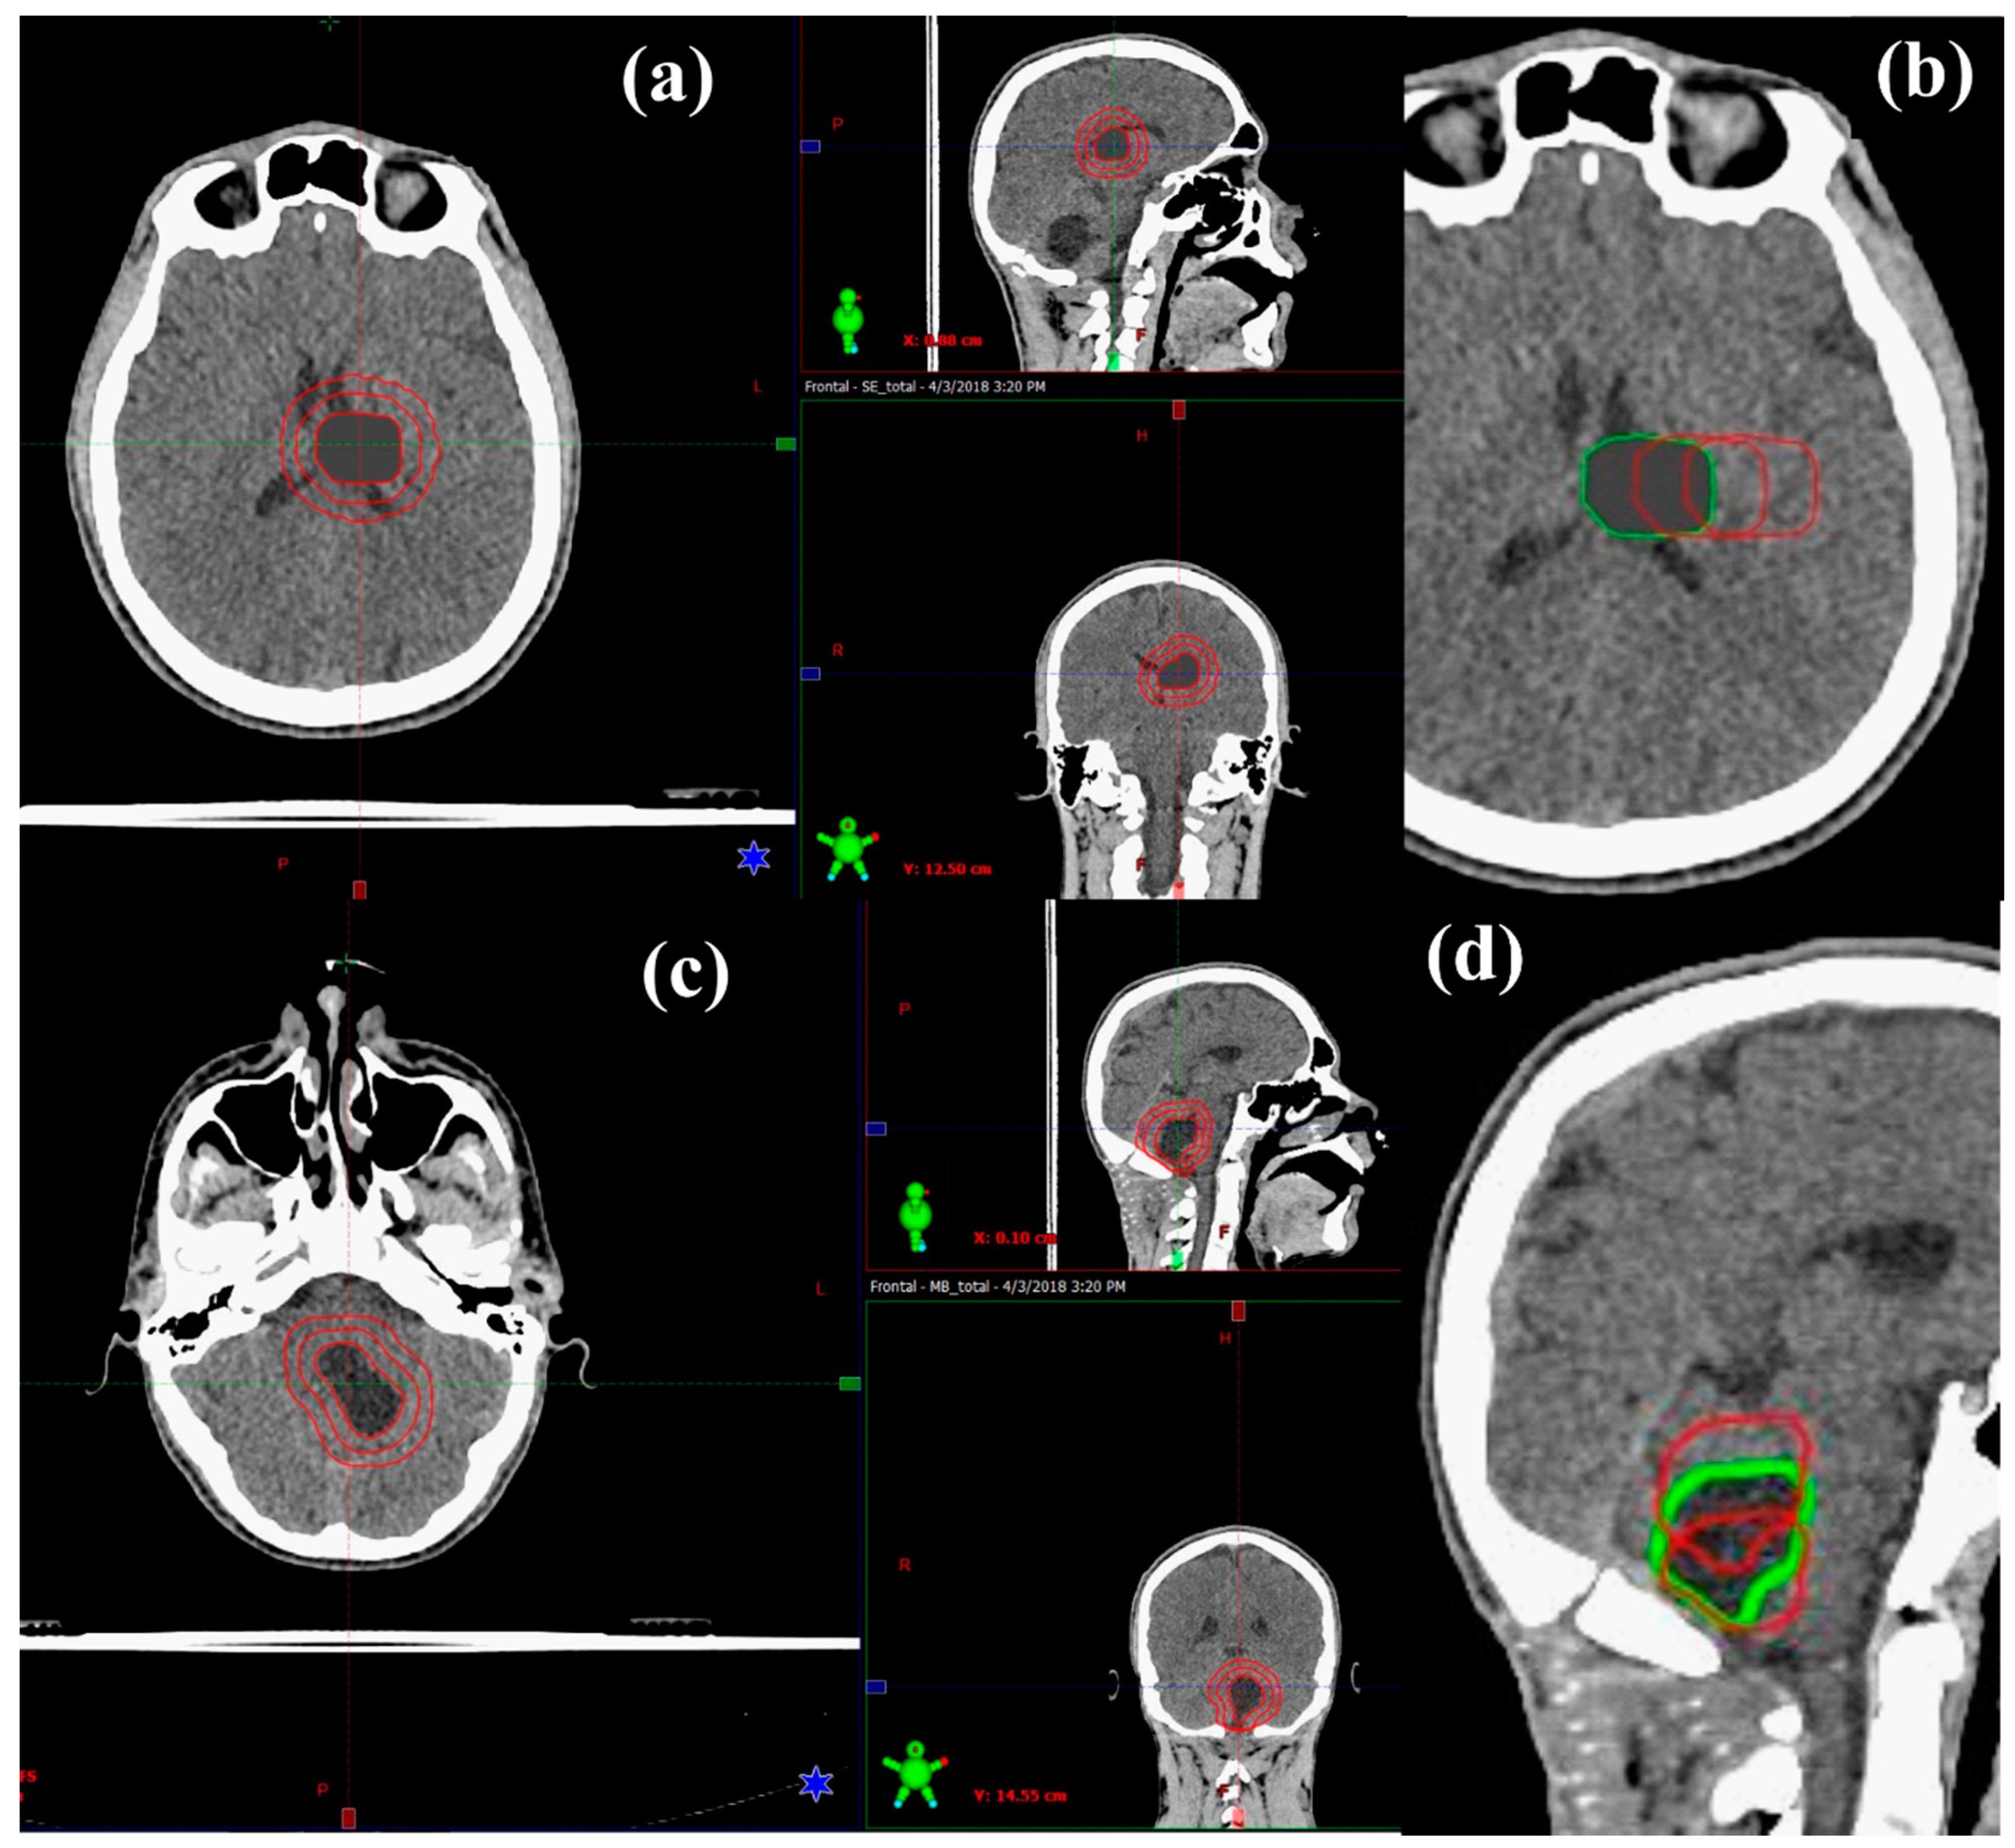

In this work, CT datasets and respective OAR contours of six paediatric patients who underwent PT with curative intent at St. Jude Children’s Research Hospital were sourced after approvals from relevant ethics committees were obtained from both institutions (St. Jude Children’s Research Hospital and University of South Australia, ethic code: 202267). Six patient datasets were used in total for this modelling study, with two datasets (female and male) for each age group (5, 9 and 13-years-old). These datasets were used as the basis of this study, minimising anatomical variability and allowing for clinical scenarios to be systematically controlled. All critical structures were previously delineated by clinicians. For modelling purposes, in this work, target volumes were added to simulate a range of volumes and shifts corresponding to the anatomical regions of the two tumours, that is infratentorial for MB and supratentorial for ependymoma (see Figure 1). MB and ependymoma were selected based on prevalence and diagnosis, as well as their common anatomic locations within the brain (infratentorial vs. supratentorial) in order to observe the impact of dose to specific normal tissue sub-volumes across the cerebral, IVth ventricle, and cerebellopontine regions. The supratentorial ependymoma (STEP) target volumes were created for each patient to represent an asymmetrical post-surgical tumour-bed volume of approximately 10 mm diameter. The MB plans followed the original clinical target volume (CTV) as a guide (prospectively delineated after surgery for each patient by a radiation oncologist). From this CTV, both target volumes were expanded (or contracted for MB) to create three variations of clinically plausible CTV diameter sizes from 1–3 cm. Similarly, this CTV was shifted, 1 and 2 cm laterally for STEP and 1 cm inferiorly and 1 cm superiorly for MB, to create three CTV locations for each tumour diagnosis. As these tumours may have different locations for different patients, the shifts represent more clinical scenarios and increase the statistical power of the datasets. This resulted in 9 simulated variations for the CTV of STEP and 9 variations for the CTV of MB for each patient. Table 1 describes all CTV variations for STEP and MB, visualised in Figure 1. Additionally, all CTVs were overridden to the density of oedema (11 Hounsfield units) to ensure consistency (post-surgical radiotherapy treatment) across simulated plans. For each IMRT plan, a 3 mm margin was applied to the CTV to create a planning target volume (PTV), whereas for IMPT plans, robust optimisation was performed directly on the CTV as PTV is not commonly used in pencil beam PT optimisation.

Figure 1. 13-year-old male (a) Supratentorial ependymoma (STEP) expansions in clinical target volumes in axial, sagittal, and coronal views (from left to right). (b) STEP variations in clinical target volume (CTV) location in axial view (green is the original). (c) Medulloblastoma (MB) expansions in clinical target volumes in axial, sagittal, and coronal views (from left to right). (d) MB variations in CTV location in sagittal view (green is the original).